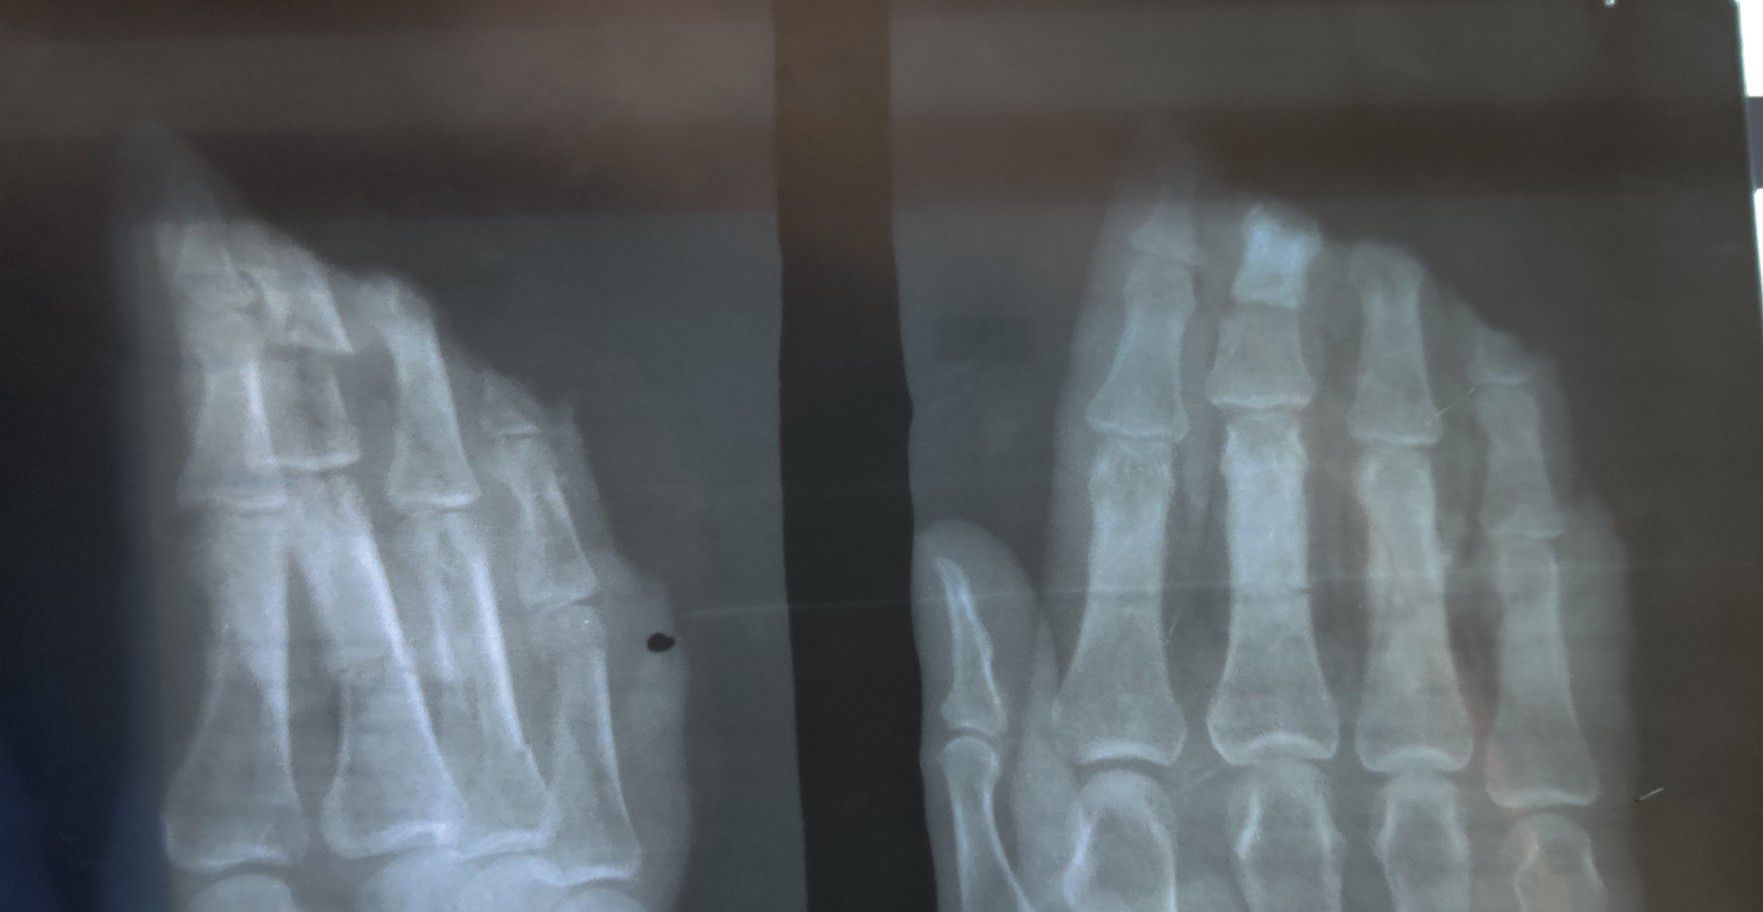

Traumatic Amputation of tips of Phalanges

Trauma

Xray

Ortho